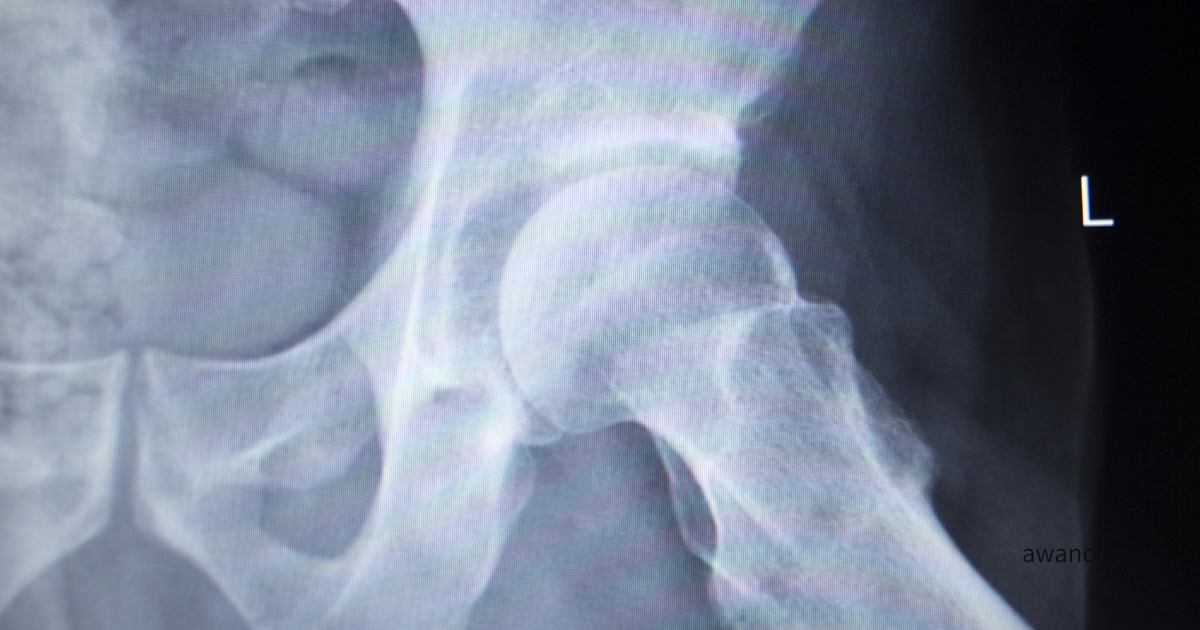

関節裂隙(関節の隙間)

軟骨はレントゲンに写らないため、関節裂隙の広さが軟骨の“残存量の目安”となります。裂隙が狭くなっている部分があれば、軟骨の厚みが減少している可能性があります。特に荷重部(体重がかかりやすい部分)の裂隙がどう変化しているかは重要です。

骨形態(臼蓋・大腿骨頭の形)

臼蓋形成不全の有無、大腿骨頭の球面性の変化、骨の形状変化などを確認します。骨形態は股関節の力学的環境を大きく左右し、将来的なリスク評価にも関わります。

骨棘形成

関節への負荷が長期間続くと新しい骨が形成されることがあります。これが骨棘です。骨棘の位置や大きさは、どの部位にストレスが集中しているかを推測する材料になります。

骨密度や硬化の有無

長期間の荷重やストレスが加わる部位では骨が反応し、硬化して白く濃く映ることがあります。反対に骨密度が相対的に低下している部分は黒く写ります。これらの濃淡分布は股関節の力学的負担の方向性を読み解く手がかりになります。

骨梁(こつりょう)という視点

骨梁とは骨の内部に存在する線状の支持構造で骨に加わる力の方向に合わせて走行しています。股関節では主に、

• 主圧縮骨梁(大腿骨頭から頚部に向かう)

• 主引張骨梁(大腿骨頭外側に向かう)

などが知られています。骨梁はレントゲンで白い線として確認できます。骨梁が濃く太く見える場合は、その部位が繰り返し負荷を受け、骨が反応して強くなっているサインと捉えられます。骨梁のパターンや明瞭さは股関節の負荷環境を判断する際の重要な情報です。

骨が白く・黒く映る理由

レントゲンの白黒は X線がどれだけ通過するかで決まります。

白く映る部分

• 骨密度が高い

• 硬化が起きている(反応性骨形成)

• 骨棘が形成されている

これらはX線を遮るため白く見えます。

黒く映る部分

• 骨密度が相対的に低い

• 軟部組織や空気

黒さそのものが問題ではなく、「どこが黒く、どこが白いのか」が重要です。